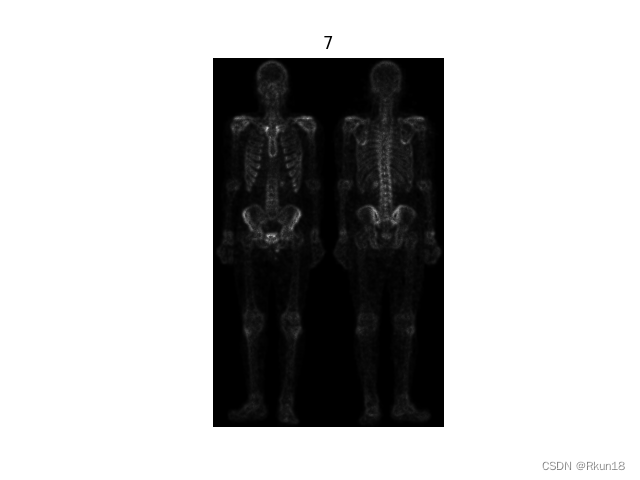

7:原图与掩蔽图像相加得到的锐化增强图像:

图像的大部分细节更清晰。